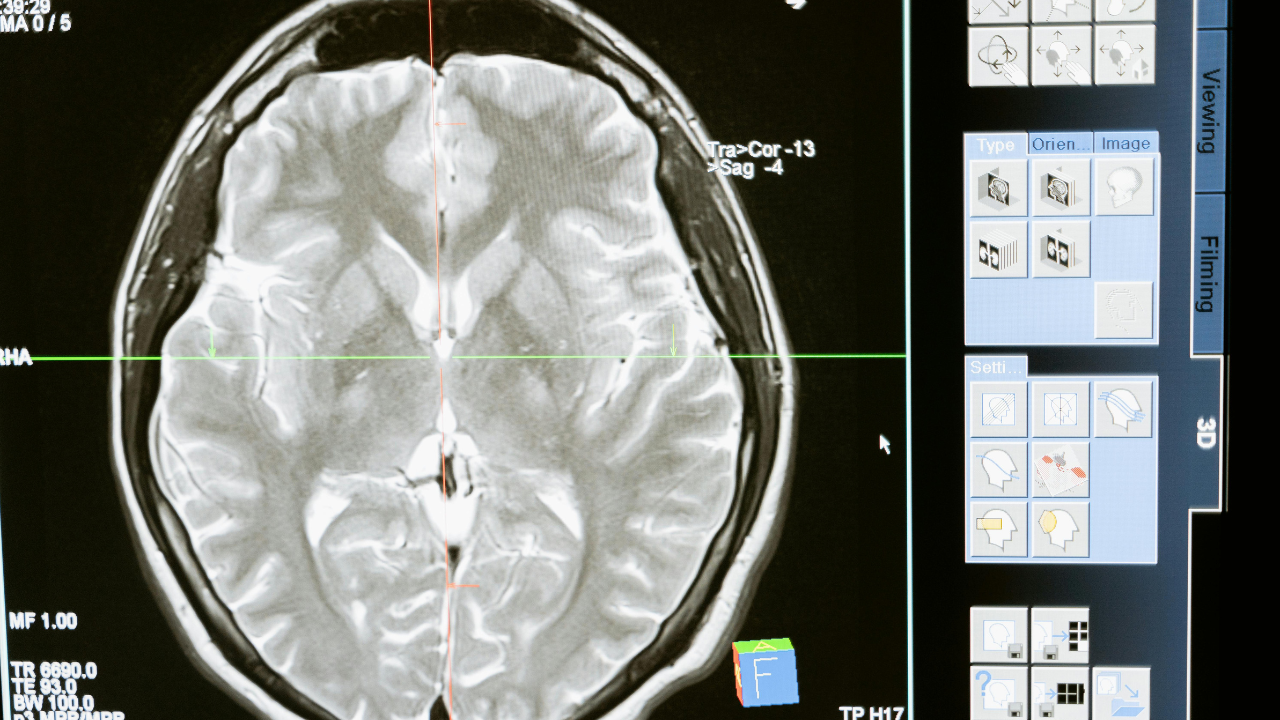

Brain Health : मस्तिष्क के लिए हानिकारक हो सकती है ये आदतें

अत्यधिक स्क्रीन टाइम आजकल, हम दिनभर अपने स्मार्टफोन, लैपटॉप और टेलीविजन स्क्रीन पर बहुत अधिक समय बिताते हैं. अत्यधिक स्क्रीन…